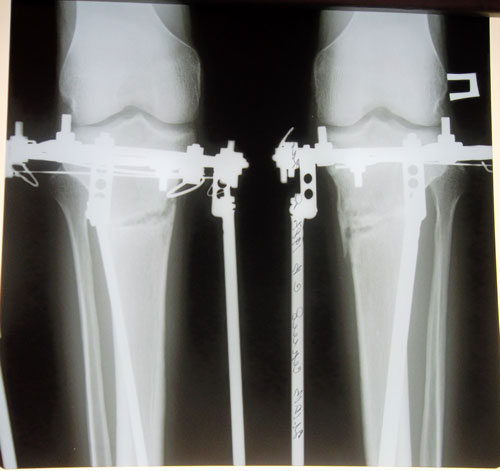

Рентген в 2 месяца.

Отличное сращение!

Вложения

SAM_6949.JPG

SAM_6948.JPG